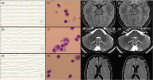

The global SARS-CoV-2 pandemic has contributed to more than 163 million confirmed infections and 3.3 million deaths worldwide. The severity of the pandemic has led to an unprecedented effort to develop multiple effective vaccines. Due to excellent safety and efficacy data from clinical trials, several vaccines were approved. We report a case series of postvaccinal encephalitis in temporal correlation to vaccination with ChAdOx1 nCov-19. The diagnostic criteria for possible autoimmune encephalitis were fulfilled. Our patients responded well to immunosuppressive therapy with corticosteroids. The incidence has been estimated to be approximately 8 per 10 million vaccine doses. Complication of postvaccinal encephalitis after ChAdOx1 nCoV-19 vaccination still appear to be very rare, but need to be diagnosed and treated adequately. Large pooled data from observational epidemiologic studies are necessary to verify causality. ANN NEUROL 2021;90:506-511.

Figures